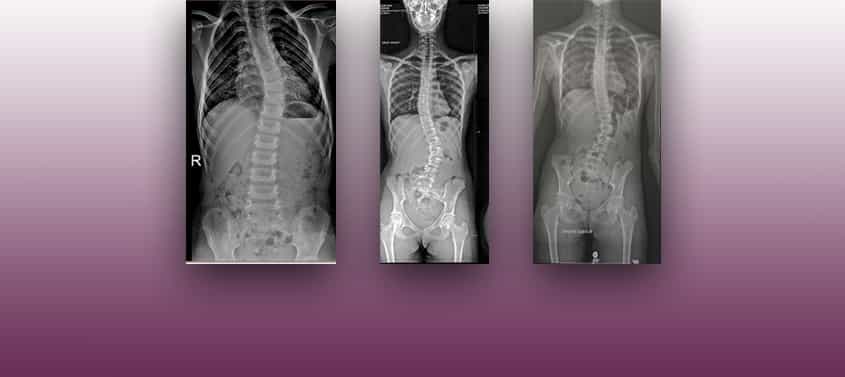

مركزنا الصحي متخصص للغاية في مرض الفيلوم ومتلازمة العمود الفقري العصبي ، وجميع الأمراض التي تشملها وتؤثر عليها بطريقة أو بأخرى في العمود الفقري، وأشهرها الجنف مجهول السبب

بالإضافة إلى الأمراض التي تسببها، يرتبط سببه بمرض الفيلوم و متلازمة التوتر العصبي الفقري

وغالبًا ما يرتبطان بأمراض أخرى في العمود الفقري؛ مثل فتق القرص والنتوءات ، وتضيق القناة الفقرية ، ومتلازمة المفاصل الوجيهية ، وخلع العمود الفقري ، ومتلازمة باستروب ، وغيرها .